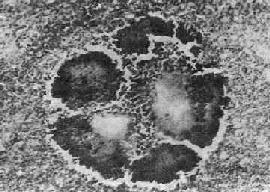

图18-36 放线菌病

病灶中的“硫黄颗粒”,周围部分菌丝排列成放线状。菌丝末端膨大呈棒状